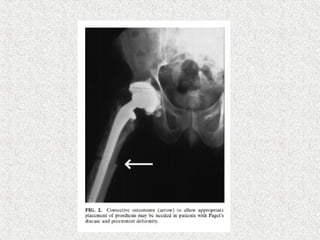

 Osteotomy to treat deformity

 Corrective osteotomy

 Severe disabling arthritis

 THR

 Significant varus deformity

 Bowing

 Acetabular protrusion

 Increased blood loss

 Distorted medullary cavity

 Sclerosis

 Heterotrophic ossification